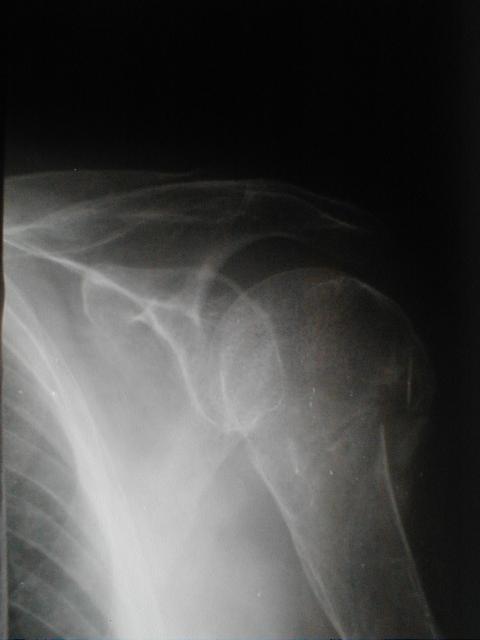

上腕骨頚部(外科)骨折と肩関節脱臼の合併症例

上腕骨頚部骨折は、高齢者に多い骨折の一つですが肩関節の亜脱臼を合併した症例において今回、保存的療法で非常に良い結果を得られたのでその整復と固定について考察を加え報告させていただきます。

左上腕骨頚部(外転)骨折

左肩関節脱臼